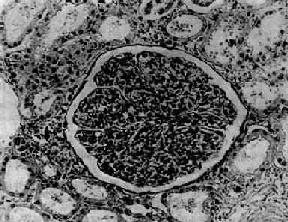

图12-7 弥漫性毛细血管内增生性肾小球肾炎 肾小球内细胞数量增多,系膜细胞和内皮细胞增生并有少量中性白细胞浸润,毛血管腔狭窄 上皮细胞一般无明显增生,少数严重的病例肾小球的壁层和脏层上皮细胞可增生,形成新月体。这种病变容易引起肾小球纤维化。如数量少,对功能影响不大。如病变广泛,可发展为新月体性肾炎。 在电子显微镜下可见肾小球系膜细胞和内皮细胞增生肿胀。基底膜和脏层上皮细胞间有致密物质沉积。这些沉积物大小不等,有的很大,在基底膜表面呈驼峰状或小丘状(图12-8,图12-9)。沉积物表面的上皮细胞足突多消失。基底膜变化不明显有时边缘稍不规则。沉积物一般在发病后几天就可出现,在4~6周内消失。有时基底膜内侧内皮细胞下和系膜内也可见小型沉积物。